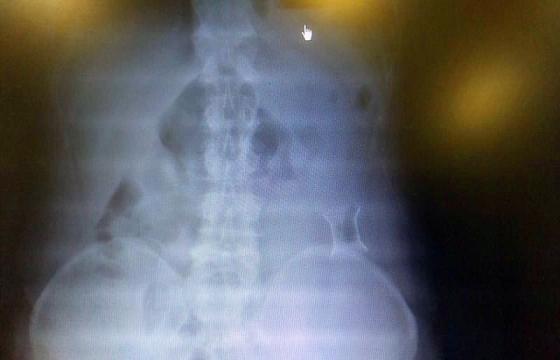

受試患者在結(jié)腸端端吻合術(shù)中,使用我司新研制產(chǎn)品達到了理想的預(yù)期效果?;颊咝g(shù)后7天、14X光片顯影,可降解腸道支架均能按研制設(shè)計的預(yù)期時間節(jié)點保持應(yīng)有強度,術(shù)后21X光片顯示可降解腸道支架已完全破碎,并排出體外。在整個試驗過程中,病患無任何不良反映,耐受良好。